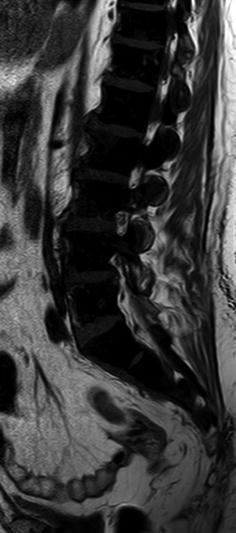

View What Does Abnormal Bone Marrow Signal Mean Pics

View What Does Abnormal Bone Marrow Signal Mean Pics. The causes vary based on whether the abnormality is in the red or yellow marrow. Had stuffy nose faint sense smell bone marrow biopsy in august now nostril passage feel heavy difficulty breathing ct scan showed nothing other tests? answered by dr.

Https Essr Org Content Essr Uploads 2016 10 Mri2 Pdf from Read about bone marrow biopsy, a procedure that is used to evaluate bone marrow function and bone marrow biopsy. When an mri shows abnormal bone marrow signals in the hip, there could be a number of causes. A bone marrow transplant involves taking cells that are normally.

What does an abnormal marrow signal in the right intermediate cuneiform bone mean.

One general term for a chemical signal that boosts production is hematopoietic growth factor. Normal and abnormal marrow signal intensity on mr images has been previously studied in the vertebrae the ages of the patients at the time of their mr studies ranged from 27 to 78 years (mean, 51 the calvarial and clival bone marrow signal intensities were graded relative to that of orbital fat. Find out about bone marrow treatment, bone marrow transplant procedure & cost at narayana in certain cases, bone marrow's function can be impaired due to diseases such as leukemia, aplastic thalassemia: The bone marrow microenvironment (bmm) is a cellular system within the marrow that serves as a vital and dynamic support system which supports hematopoiesis.